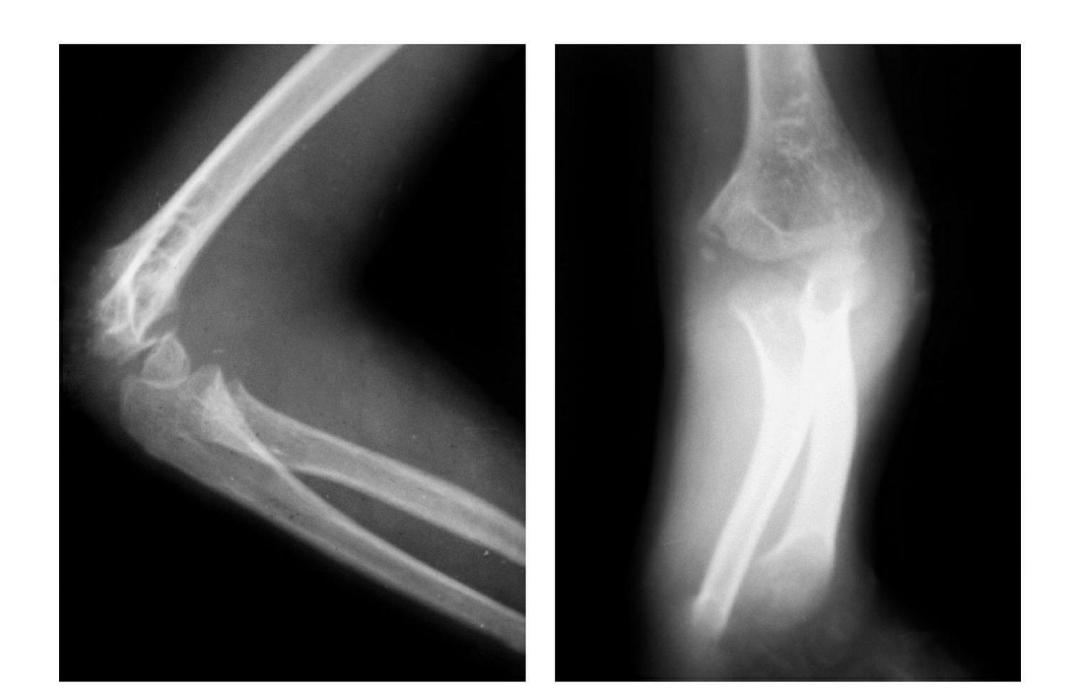

(4)Monteggia 骨折

1814 年 Monteggia 首先描述了这种骨折类型,是指尺骨上 1/3 骨折合并桡骨头向前脱位的一种联合损伤。

1967 年 Bado 进一步完善 Monteggia's 骨折的概念,即任何部位的尺骨骨折合并桡骨头脱位。

后来随着人们对这种损伤机制的进一步研究.使该损伤概念的范围逐渐扩大,将桡骨头各方向脱位合并不同水平的尺骨骨折或尺、桡骨双骨折都列入。